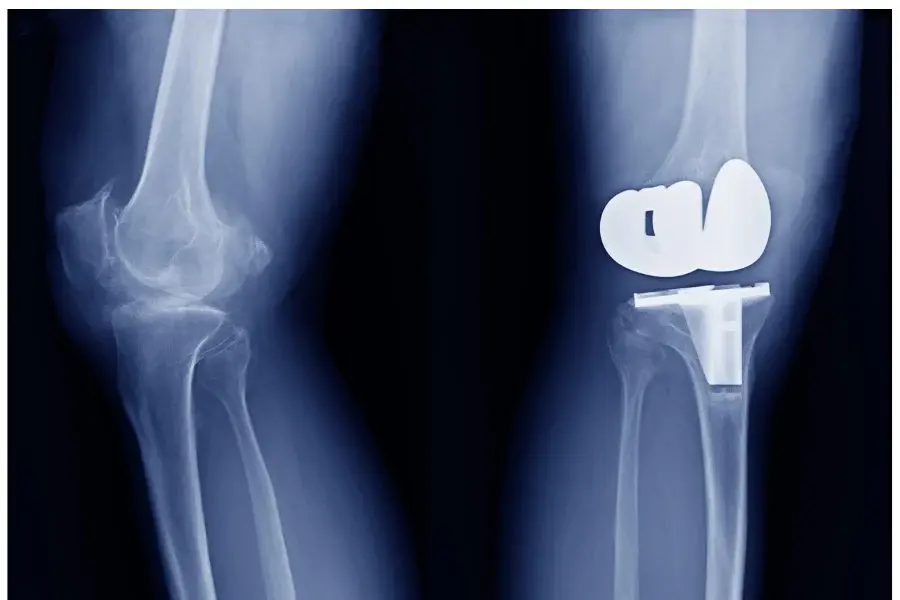

• Total or partial knee replacement in advanced cases of osteoarthritis